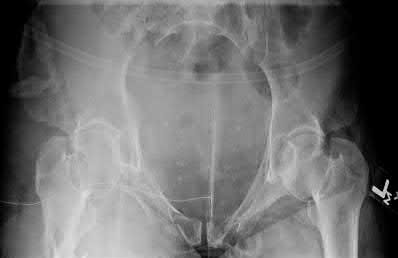

A 35 year-old female presents after prolonged extrication from a motor vehicle collision complaining of severe pelvic pain. Physical examination reveals diminished perianal sensation. She is otherwise neurologically intact. Figures A through D are radiographs and representative CT cuts of her injury. Which of the following nerve roots has likely been injured by the acute trauma?

The clinical scenario is consistent with a high-energy sacral fracture. The radiographs in figures A and B demonstrate a sacral fracture with posterior displacement of the right hemipelvis seen on the inlet view. Figures C and D are axial and sagittal CT images which show a displaced fracture of the right

hemisacrum along with a transvere fracture component through the S3 body . Diminished perianal sensation is concerning for an S2 nerve root injury.